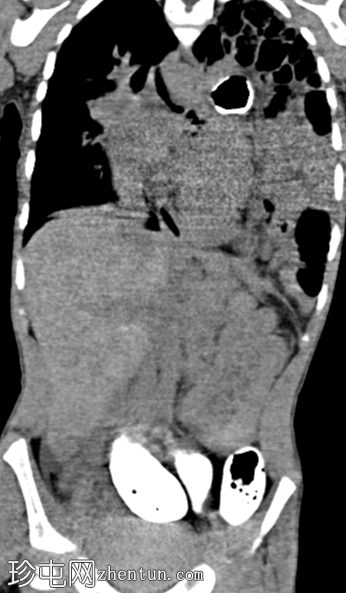

荧光透视

正面

斜位

消化道造影检查显示食管口径正常,胃明显延长,延伸至盆腔区域。

左胸腔可见囊性透亮区,与腹部相连,导致心脏轮廓向右侧移位。